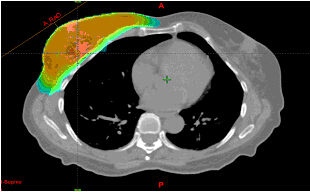

(4)IMRT调强放疗增加了心脏的平均剂量

14位患者的(a)调强适形放疗和(b)三维适形放疗计划的心脏剂量分布图。 尽管,对于剂量大于30Gy的治疗调强适形放疗的心脏剂量是最小的,但与三维适形放疗计划相比,平均和中位心脏剂量却升高了。